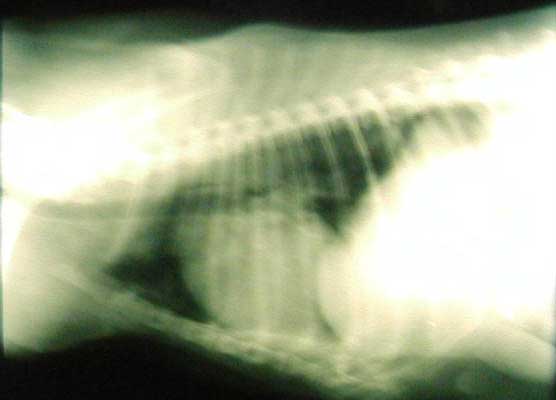

Esame radiografico del torace in proiezione latero-laterale

di un cane razza boxer sesso m. anni 5 (cinque). Notasi l'alterazione

della silhuette cardiaca e della trama bronco vasale. Ipertrofia atriale

dx e ventricolare dx, vena cava caudale dilatata.

Withness positivo per FCP. Snap heartworm: alto livello di antigene.